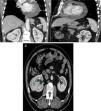

Dado a presença de derrame pericárdico e a massa cardíaca realizou TC toraco‐abdomino‐pélvica para caracterização da mesma e exclusão de neoplasia associada, a qual confirmou a existência de uma lesão captante de contraste em proximidade da aurícula direita (Figura 3A), bem como uma outra lesão nodular sólida a nível do rim direito sugestiva de neoplasia renal (Figura 3B). Realizou, igualmente, ressonância magnética cardíaca (RMC) e abdominal que não foi conclusiva relativamente à lesão cardíaca (lesão primária versus secundária), mas que confirmou os aspetos sugestivos de neoplasia renal primária da lesão abdominal.